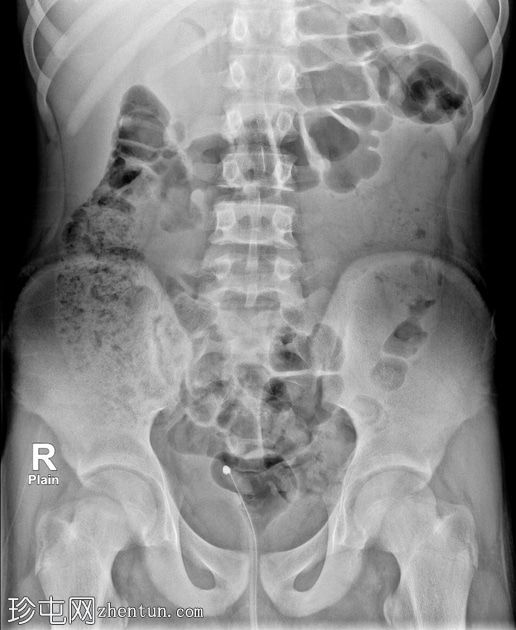

年龄:15岁

性别:男

通过导尿管注入造影剂后,可见膀胱延长,膀胱壁不规则,呈小梁状,并有多个大小不一的外囊。

排尿后序列中可见残余尿液。

本病例展示了

神经

源性膀胱的临床和放射学特征。